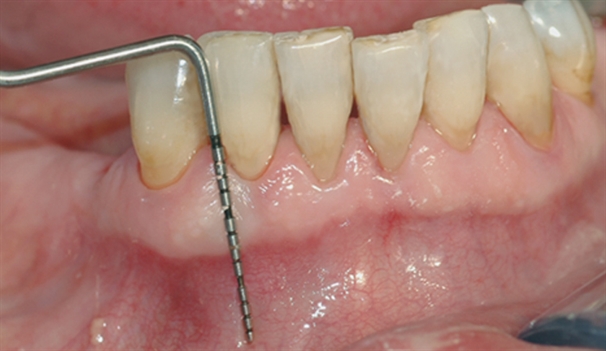

• perio stor 2

perio stor 2

En undersøkelse med lommeregistrering avdekker likevel et omfattende bentap ved den ene tannen.